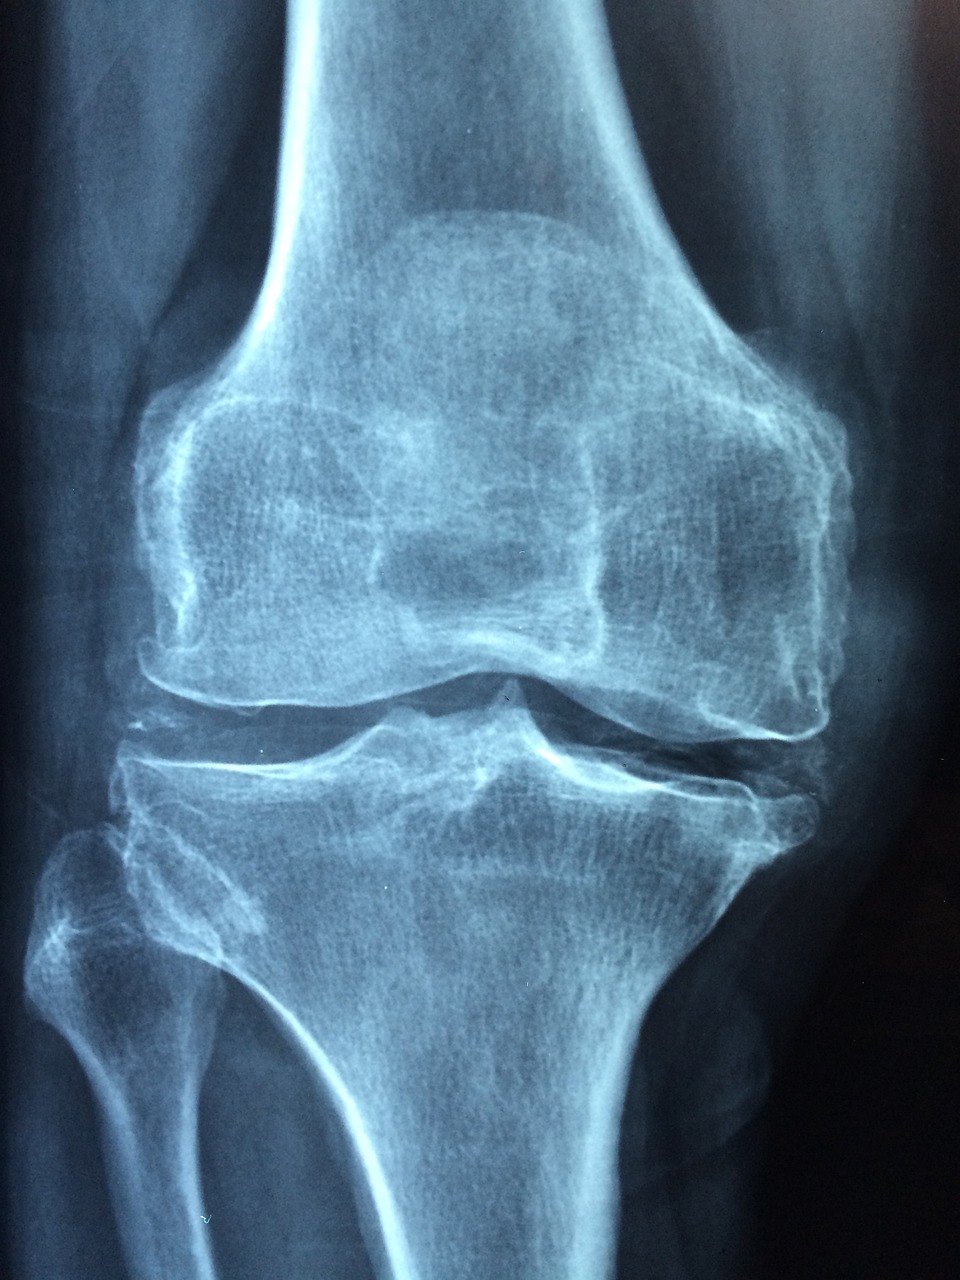

무릎 뒤쪽 통증 (치료법은?)

오늘은 무릎 뒤쪽 통증으로 인해 걱정되시는 분들을 위해 무릎 뒤쪽 통증 원인과 치료법에 대하여 말씀드리도록 하겠습니다. 이 글을 통해 원인을 찾아보고 치료법까지 알아가는 시간 가지셨으